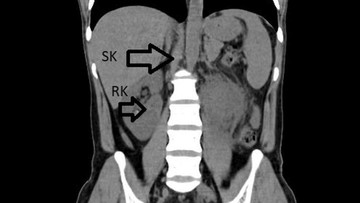

"Pasien tersebut memiliki ginjal tambahan," tegas salah satu sumber medis yang terlibat dalam penanganan kasus langka ini. Penemuan ini menjadi bagian penting dari diagnosis komprehensifnya.

Kondisi memiliki organ tambahan, seperti ginjal ketiga, merupakan sebuah kelainan bawaan yang jarang sekali terdeteksi, apalagi saat pasien datang dengan keluhan infeksi biasa. Temuan ini mengubah fokus penanganan medis secara keseluruhan.